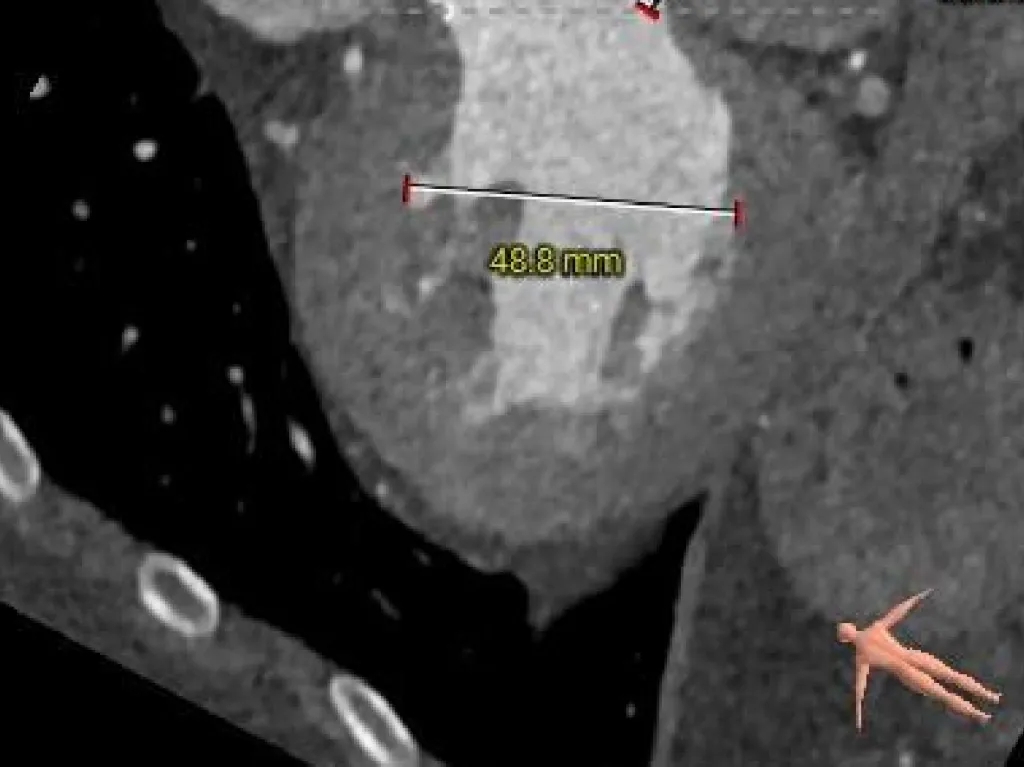

术前CT分析

主动脉根部测量

Annulus-收缩期

30.3mm

Annulus-舒张期

29.9mm

LVOT

30.8mm

sinus

STJ

46.1mm

AAO

53.7mm

Type-0型二叶瓣

瓣环径约30.3mm

微敞口型流出道

瓣叶增厚

交界缘钙化分布

瓦氏窦扩张

升主瘤样扩张